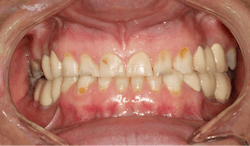

A 35-year-old female patient presented with esthetic concerns after a diagnosis of Sjögren's syndrome. Patient complaints included short appearance of teeth, stained teeth, and worn incisal edges (figures 1–2). Loss of vertical dimension of occlusion was noted as evidenced by shortened coronal structure and bilateral angular cheilitis (figure 3).

After the first phase consisting of caries control and periodontal treatment, the patient received soft- and hard-tissue crown lengthening by laser (figure 5). After an eight-week healing period, full-mouth cosmetic restorations were placed, which included full- and three-quarter-coverage e.max crowns and zirconia bridges (figures 6–7).

Following therapy, the patient was seen every three months for hygiene recare and to evaluate the status of caries and gingival inflammation. CariFree CTx4 Gel, home-administered sodium fluoride trays, and interproximal irrigators were given to the patient to increase resistance to caries. Oral hygiene instruction was an integral part of the recare visits and proved to be valuable in maintaining the patient’s results two-and-a-half years later (figure 8).